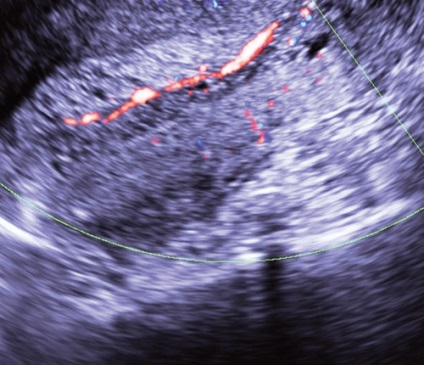

A különböző szállítási módok és a Doppler véráramlás képalkotó nedopplerovskoy valóban lehetővé teszi számunkra, hogy azonosítsuk a vaszkuláris kocsány a polip (ábra. 9), kivéve, ha nincs jele a hámlás az endometrium. Ebben az esetben a (ábra. 10) mozgását a vér az üregben a méh és a méhnyak lehet szimulálni a vér áramlását az erek a polip lábak és regisztrált a készülék kijelzőjén, mint egy hasonló színjelek.

Ábra. 9. A kocsány nyaki polip CDM módban.